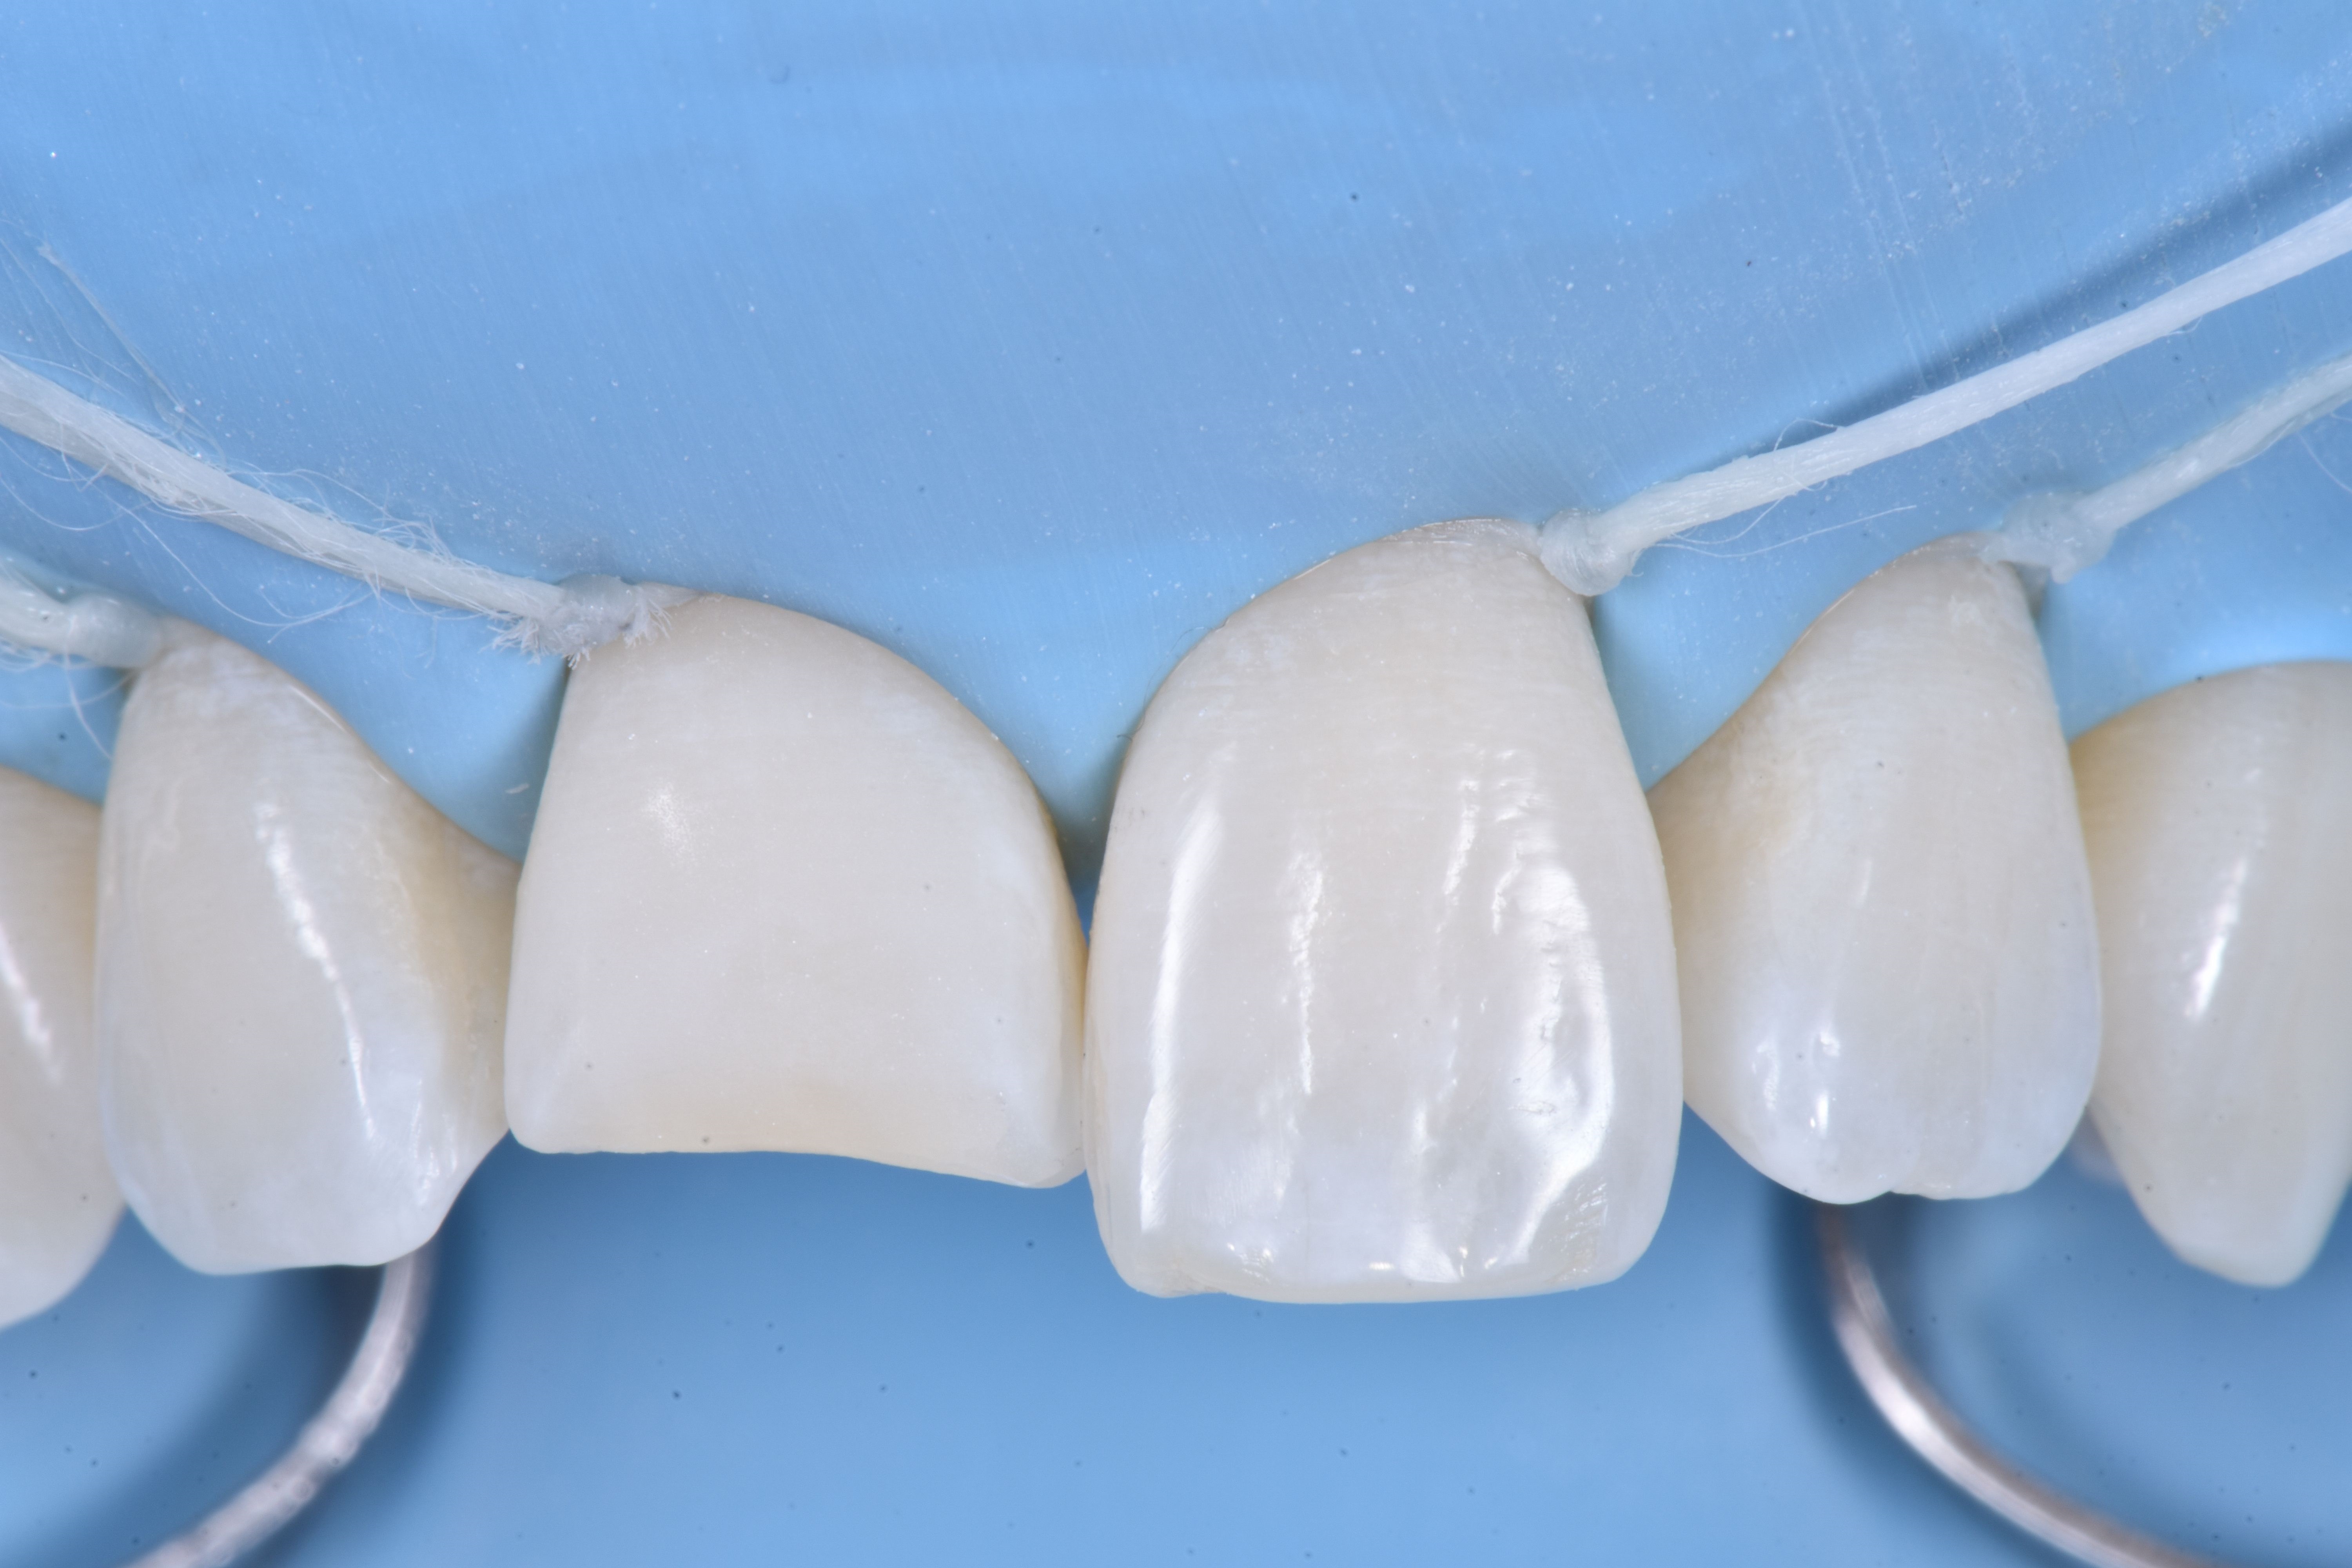

W celu skorygowania zaburzonego biernego wyrzynania zdecydowano się odtworzyć profil wyłaniania poprzez zaakcentowanie wypukłości przedsionkowej, dążąc do upodobnienia go do zęba sąsiedniego.

W tym celu zastosowano wstępnie uformowaną metalową formówkę, którą ufiksowano dwoma klinami.

Przedsionkowy profil wyłaniania odtworzono kompozytem w odcieniu szkliwa (ESTELITE ASTERIA WE firmy TOKUYAMA DENTAL) (ryc. 7).